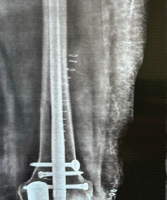

Radiographs revealed a comminuted fracture at the base of the middle phalanx with dorsal subluxation. The injury was treated with a Suzuki frame comprising the following:

- 1.2 mm axial traction pin through the proximal phalanx head

- 1 mm hook pin through the distal middle phalanx

- 1.2 mm reduction pin dorsal to the fracture site.

Sterile intravenous tubing was used to provide adjustable dynamic tension. Intraoperative fluoroscopy confirmed alignment. A post-operative structured hand therapy protocol was initiated under physiotherapy guidance, including passive and active range-of-motion exercises starting within the 1st week (Fig. 2-4).